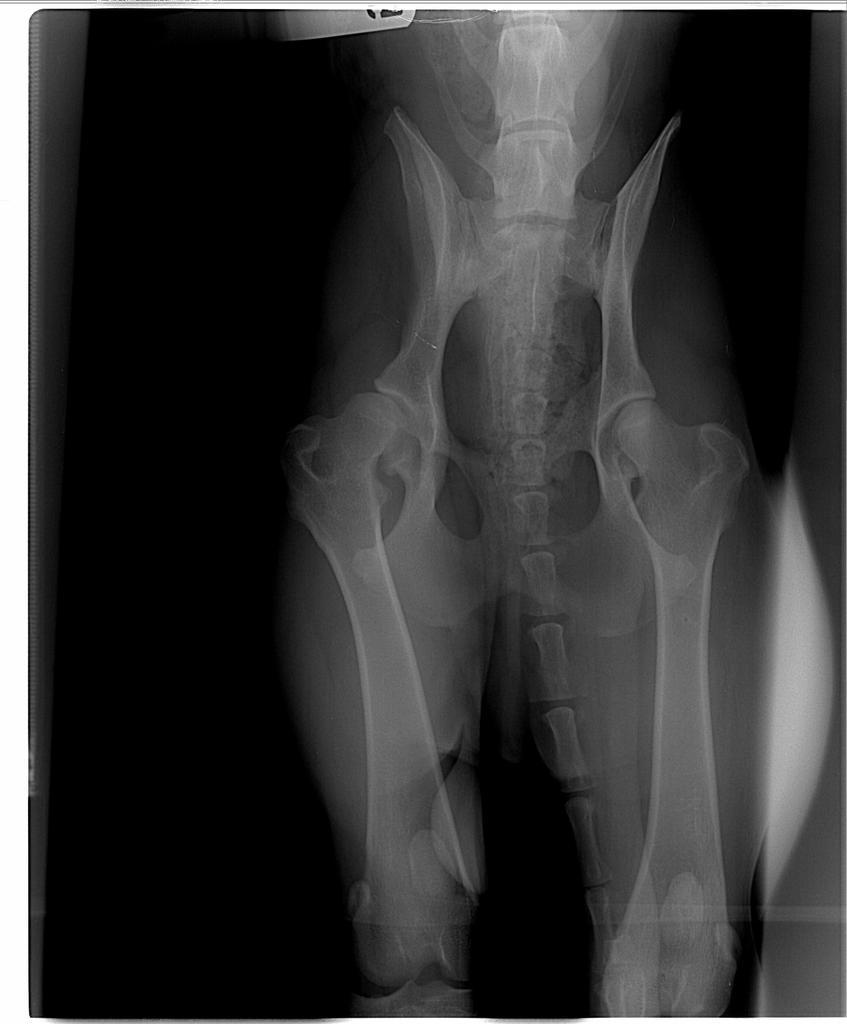

ewula Posted November 20, 2008 Author Posted November 20, 2008 Jesteśmy "po", ale niestety jednak o TPO trzeba było zapomnieć :shake: - zbyt mała miednica, kość trzebaby pod jakims nienaturalnym kątem ustawiać co mogłoby być dyskomfortem podczas poruszania się , wręcz krzywdą dla pieska - najogólniej chodzi o to ze mógłby mieć tę łape tylko w jednej pozycji, tzn. prosto a w bok nie mógłby jej podnieść, np. przy siusianiu. Więc niestety ta metoda odpadła, można było to stwierdzic dopiero przy badaniu go juz po uspieniu. Była więc obustronna daroplastyka, mam nadzieję że wszystko dobrze, choć na to prawe biodro to było ryzyko. Jestem w domu, po 20 mam dzwonić. Zostawiłam go w klinice, lekarz stwierdził że to doskonały pomysł, że go nie zabieramy tak szybko. Ale pewnie w sobotę po niego pojedziemy, z tęsknoty... Odezwe się po 23 albo dopiero jutro rano... Dzięki za trzymanie kciuków :loveu: Quote

AgaCzarna Posted November 26, 2008 Posted November 26, 2008 Bracia wrocili z Wroclawia...specjalista wypowiedzial sie,ze wada jest bardzo powazna zwlaszcza 1 biodra,ktore nie nadaje sie na operacje...za plytka panewka i juz zaczelo robic sie zwyrodnienie...Moze byc tak,ze za pol roku w ogole przestanie chodzic...juz teraz go bardzo boli...Niestety pozostaje tylko uspienie:-(:-(:-(:-(:-( 3mam kciuki za tych ktorym sie udalo Quote